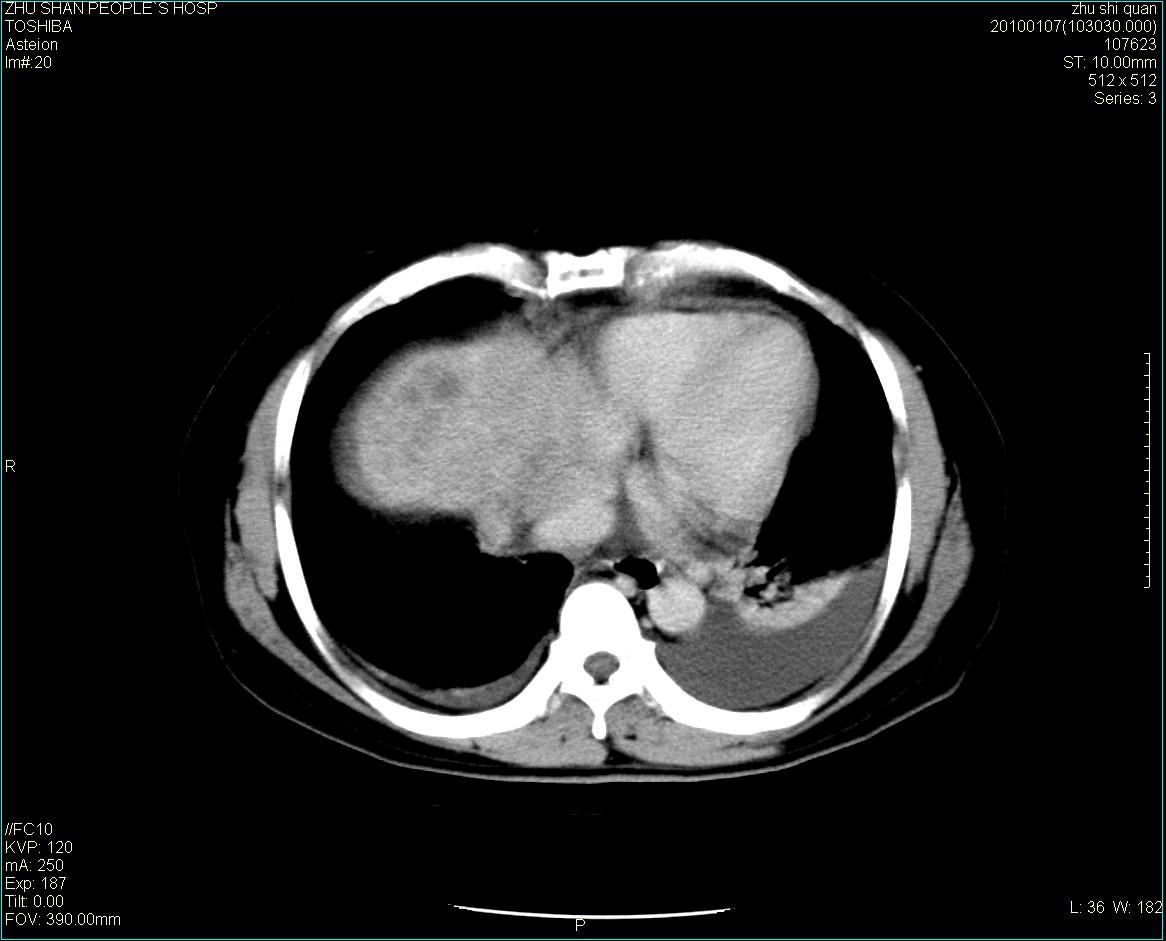

男性病人 肝ca两次术后,今日复查。

1)肝癌并多发性转移。2)双侧胸腔积液(以左侧为甚)伴左下部分肺萎陷。

肝癌术后复发,肝内、脾脏、腹膜后及腹膜多发转移,腹水,双侧胸腔积液(以左侧为甚)伴左下膨胀不全。

肝癌术后复发,肝内、脾脏、腹膜后及腹膜多发淋巴结转移,腹水,双侧胸腔积液。